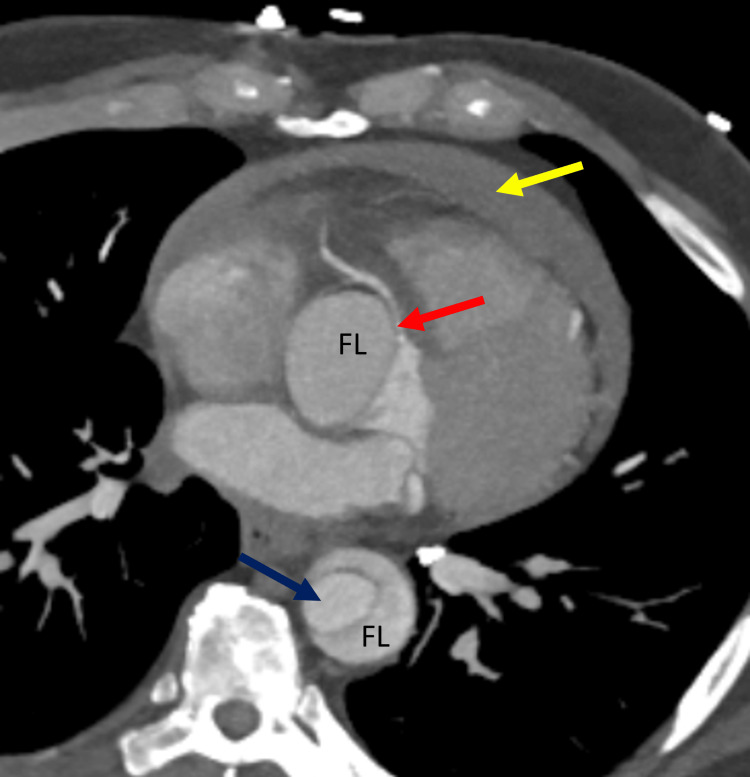

In view of chest pain associated with positive cardiac biomarkers, he was admitted to the Coronary Care Unit on intravenous nitroglycerin. While waiting for his admission, he suddenly had recurrent chest pain associated with marked hypotension (75/43 mmHg), for which the intravenous nitroglycerin was discontinued, fluid resuscitation was provided, and he was temporarily started on intravenous norepinephrine. The on-call cardiology team was contacted for an emergent evaluation. Subsequent ECG showed nonspecific ST-segment changes in leads V5-V6 (Figure 1). An emergent bedside echocardiogram revealed a moderate pericardial effusion of hemodynamic significance (Figure 2), as suggested by partial right ventricular chamber collapse (Figure 3) early in diastole and a plethoric non-collapsing inferior vena cava. The pericardial effusion also contained echogenic strands, which are highly concerning for blood clots. Additionally, a moderate to severe aortic valve insufficiency (Figure 4) was present according to color Doppler findings and pressure half-time assessment (315 ms). An intimal flap was visualized on the ascending and descending aorta, suggesting an extensive AD (Figures 2–6). A computer tomographic angiogram (CTA) of the chest and abdomen revealed a large pericardial effusion with an extensive AD extending from the level of the ascending aorta into his right brachiocephalic artery, the right and left common carotid arteries, and inferiorly to the right iliac artery (Figures 7–10), although not occlusive in diameter (or clinically). These findings were consistent with an extensive Stanford type-A AD with rupture into the pericardium, for which volume expansion and vasopressors were provided and emergently operated on the same day. The surgery included an open pericardiotomy with pericardial blood drainage, replacement of the ascending aorta from just above the commissure to the take-off of the innominate artery, partial replacement of the aortic arch, and aortic valve repair with successful results. Multiple intraoperative packed red blood cell units (8), fresh frozen plasma units (4), cryoprecipitate units (10), and platelet apheresis (3) were provided in view of bleeding complications related to the arrival provision of dual antiplatelet and anticoagulation therapy prior to the diagnosis of AD.